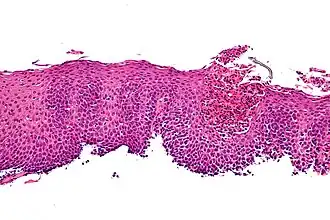

Infiltratie van het slokdarmslijmvlies met eosinofiele granulocyten

Om de diagnose vast te kunnen stellen moet volgens de huidige richtlijnen op drie niveaus in de slokdarm, in de maag en in de twaalfvingerige darm een weefselhapje (biopt) worden afgenomen. Met behulp van een microscoop worden deze weefselhapjes door de patholoog beoordeeld. Hierbij wordt specifiek gekeken naar de aanwezigheid van eosinofiele granulocyten. De patholoog telt het aantal eosinofiele granulocyten per weefselhapje en kijkt hier naar met een microscoop bij een vergroting van 400 x. Het veld dat met deze vergroting wordt gezien noemen we een gezichtsveld of “High Power Field (HPF)”. De algemene afspraak hierover is dat de diagnose kan worden gesteld wanneer er in een weefselhapje sprake is van 15 of meer eosinofiele granulocyten per gezichtsveld (HPF).